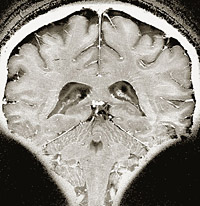

Международная группа нейрофизиологов Оксфордского университета разработала методику томографии, позволяющую предугадать намерения человека еще до того, как он начнет действовать. Эксперимент был прост: ученые просили добровольцев по собственному усмотрению сложить либо вычесть числа, которые им показывали на экране. Одновременно проводилось сканирование мозга испытуемых, после чего полученные томограммы были обработаны с помощью компьютерной программы, призванной вывести общий алгоритм мозговой активности в моменты принятия простейших решений.

«В ходе исследования были обнаружены так называемые метки активности в медиальной предлобной коре головного мозга, — говорится в отчете руководителя экспериментов профессора Джона-Дилана Хайнза из Института когнитивных проблем и нейрофизиологии им. Макса Планка. — Причем у 70 процентов испытуемых реакции изменения активности были одинаковыми в зависимости от того, намеревался ли человек вычитать числа или складывать их».

Это, в свою очередь, позволило исследователям заявить о разработке первой, пусть пока и примитивной, технологии чтения мыслей. Однако, как опасается профессор Хайнз, эту методику могут быстро взять на вооружение спецслужбы в добавление к уже имеющемуся арсеналу «детекторов лжи». Поэтому уже в этом году будет создано Общество нейроэтики для обсуждения последствий исследований мозга.